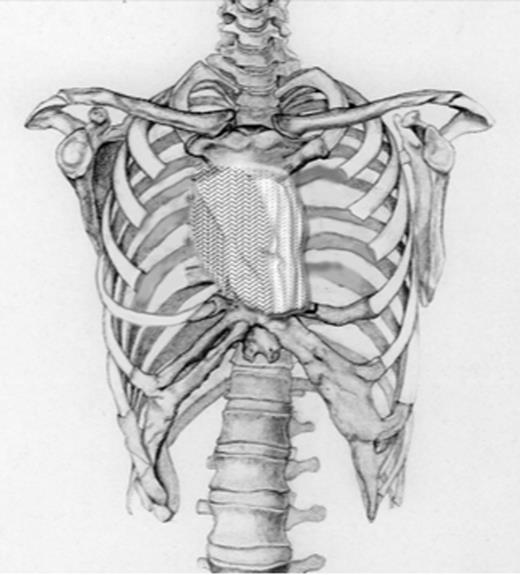

A 60-year-old male patient presented himself to the outpatient clinic of our department with a progressive sternal mass. An MRI scan indicated a tumour involving the manubrium extending to the first and second ribs and involving the right clavicle and sternoclavicular joint (Figs 1 and 2). Based on radiological evaluation, a core biopsy was obtained and a low-grade chondrosarcoma was characterized. Radiological evaluation indicated primary tumour resection to be the treatment of choice. Radical excision of the tumour was performed and resulted in resection of the manubrium, as well as the medial third of the right clavicle and the right first and second ribs. Steel wires through the sternum and left sternoclavicular joint spanned the 6.5 cm sternal defect (Figs 3 and 4) and a polypropylene mesh filled with methyl methacrylate composite (Surgical Simplex®), Howmedica Osteonics, Limerick, Ireland, was placed, yielding a stable reconstruction of the sternal defect (Figs 5–8). The sternocleidomatoideus muscle was re-inserted to the polypropylene mesh. Pathological examination showed complete excision of the tumour. The patient recovered uneventfully and was discharged 7 days post-operatively. At seven year follow-up, the patient displayed excellent functional and aesthetic results. Optimal function of his shoulders allowed a complete return to work and other activities without disabilities.

Schematic drawing of the size of the defect after radical excision followed by placing steel wires through the stenal ends.

This picture shows the size of the defect in the patient after radical resection, which was 6.5 centimetres. Consequently, steel wires were placed through the sternal ends and the left sternoclavicular joint and a polypropylene mesh was place on the surface of the defect.